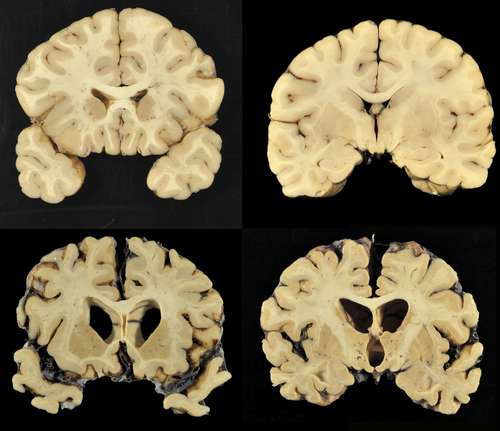

Examinaron 202 casos y 177 fueron diagnosticados con encefalopatía traumática crónica, padecimiento vinculado con reiterados golpes a la cabeza, señala el reporte publicado ayer